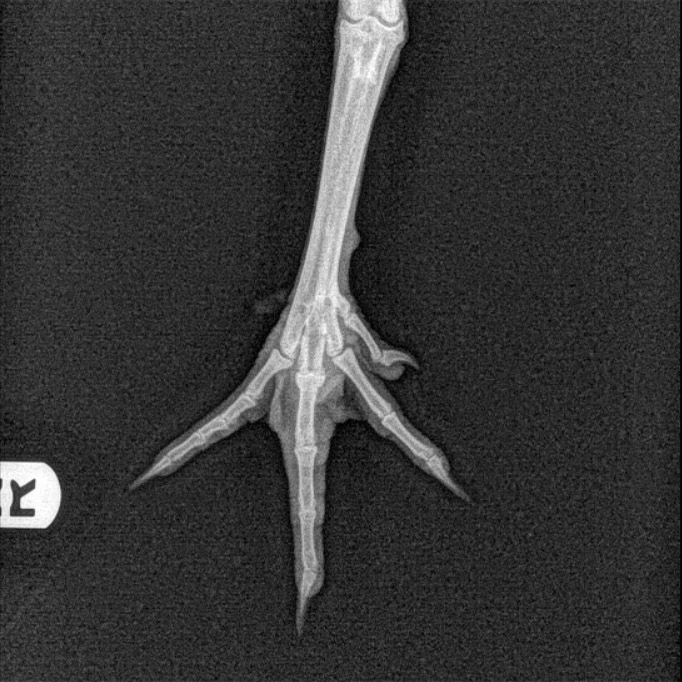

Once Dr. Strickland reviewed the radiographs, he informed Kelly that Checkers had a non-displaced fracture of the middle digit on the first phalange in his right foot. He also showed Kelly the radiograph and pointed out exactly where the fracture was located. Dr. Strickland explained how that since it was a minor fracture, Checkers would be okay without a splint or bandage and that the lesion would likely heal in 2-3 weeks.

Radiograph of Checker’s fracture